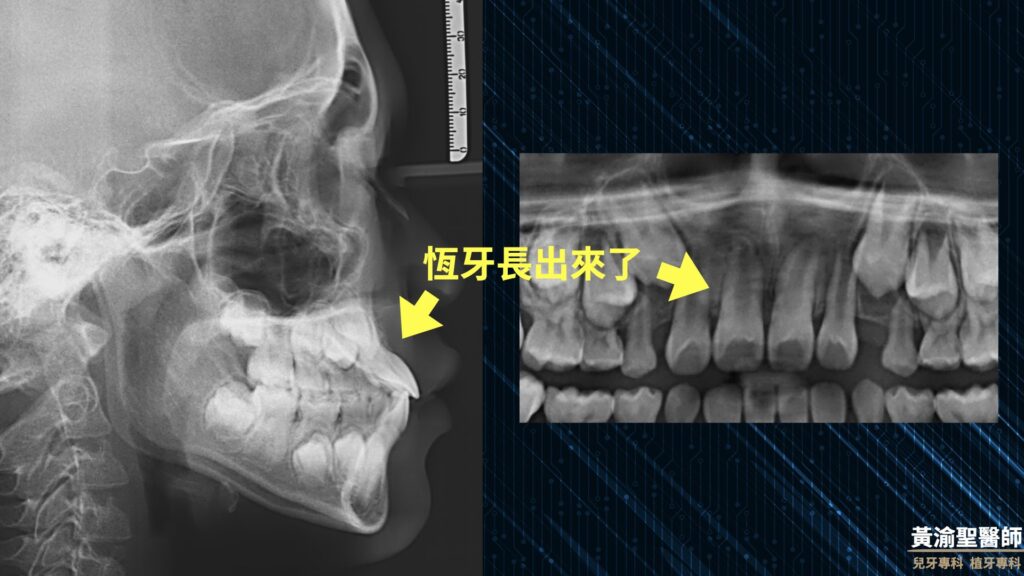

0 評論 0 FacebookTwitterTelegramLINEEmail 自上次分享前牙阻生的知識後 小黃醫師門診突然多了好多前牙有狀況的孩子 這次小黃醫師用一個臨床案例與您分享 如何治療前牙阻生 小陳年方8歲 曾有乳牙撞傷歷史 由圖可見前牙發黑 牙齒遲遲不掉 媽媽很擔心 有受傷歷史且對稱牙齒已長超過半年 這時候小黃醫師心中的警鈴已經叮叮想起 腦中浮現抖音神曲叮叮噹噹 接著就跳了起來 這首歌很洗腦 從各式影像檢查就可以發現 門牙很有個性的往前長 這樣的狀況當然需要介入治療 趕快先拔掉變色的乳牙 觀察3個月 發現恆牙並沒有改善位置 進入矯正治療 首先黏上矯正器讓每顆牙齒乖乖站好 幫阻生門牙留下足夠的空間 接著就辛苦小陳了 小黃醫師會開個小小的刀 恩就算很難 也會跟小朋友說小小的刀 (不過跟植牙牙周手術相比, 阻生齒手術真的簡單很多) 幫阻生門牙黏上一顆矯正器 慢慢的有耐心的拉出來 最後終於還給小陳帥氣的微笑 如果您對於孩子是否有前牙阻生感到擔心 不妨參考小黃醫師上一篇文章歐 門齒阻生-門牙長不出來 多數情況及早發現 都能得到很好的治療結果 定期檢查超重要 每次少少的掛號費 就是避免大問題突然出現 讓孩子經歷莫大的辛苦 謝謝您的觀看 也歡迎分享給小孩正在就讀小一的朋友歐 #黃渝聖醫師 #一分鐘小常識 #不看字就看圖 #兒童牙科 #美容牙科 #口腔衛教 #植牙專科 #兒牙專科 #家庭牙科專科 #員林基督教醫院 #彰化基督教醫院 #兒童早期矯正 #MRC #肌功能訓練 返回首頁 MRC一分鐘小常識不看字就看圖兒牙專科兒童早期矯正兒童牙科口腔衛教員林基督教醫院家庭牙科專科彰化基督教醫院植牙專科美容牙科肌功能訓練門牙阻生門齒阻生黃渝聖醫師 0 評論 0 FacebookTwitterTelegramLINEEmail 上一篇 門齒阻生-門牙長不出來🥺 下一篇 小兒常見牙科藥物與蠶豆症 你可能也會喜歡 兒童早期矯正-努力才能讓你的... 牙齒的溜滑梯-咬合斜坡 全口蛀牙重建-睡覺治療 醒來你... 陶瓷嵌體-保留齒質的好方法 乳牙小鋼牙 兒童早期矯正 前牙錯咬 地包天-前牙錯咬 早期矯正治療 矯正會不會「超級痛」? 前牙逆向錯咬 牙齦萎縮 兒童早期矯正 前牙錯咬